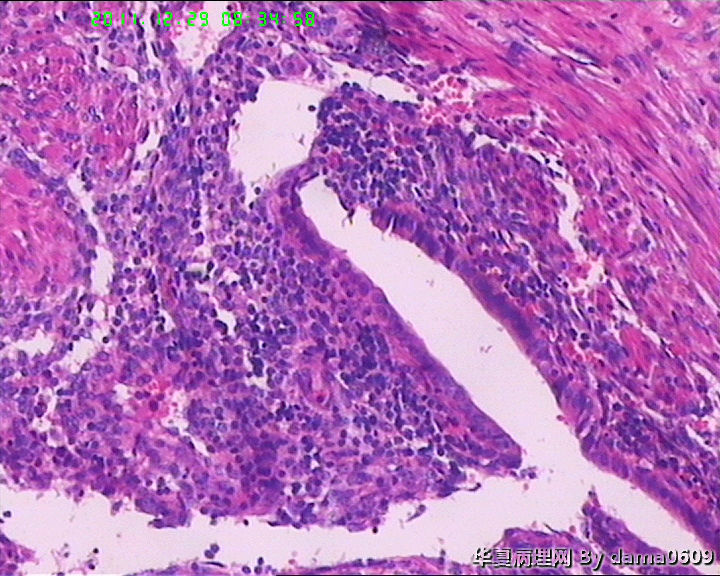

另一为小块囊壁样组织。镜下见卵巢间质内大量淋巴细胞、嗜酸性粒细胞浸润,间质出血。囊壁囊腔一侧见组织细胞、嗜中性粒细胞浸润,小血管增生(图1-9)。局灶见较多的平滑肌组织,内见有异位的子宫内膜组织(图10、11、12)。另于平滑肌组织间见到散在的小腺体(图13~30)。学生不解:1、老年人卵巢内可以出现平滑肌组织,如卵巢门处。此例如此多的平滑肌是正常的吗? 2、平滑肌间的小腺体若是异位的子宫内膜腺体但周围不见内膜间质成分。若非内膜异位腺体,学生又不知如何解释,尤其图19、20、21。请老师们指点迷津。感谢!!

这种现象很常见(你可以在很多由于卵巢癌或者子宫内膜癌患者切除的卵巢周围看到这种现象,当然不包括炎症),我认为不是自溶。前面的一些腺体可以认为是苗勒管,就好比我们在宫颈深部可以看到这些腺体一样,这是一种正常现象,贴着平滑肌边上的腺体也是苗勒管腺体,有可能是卵巢囊肿感人带的输卵管成分,或者就是卵巢门部的一些苗勒管。我不认为是子宫内膜异位,关于异位一说,有子宫内膜异位,子宫颈内膜异位,还有输卵管内膜异位(大多数认为是苗勒管残余形成)